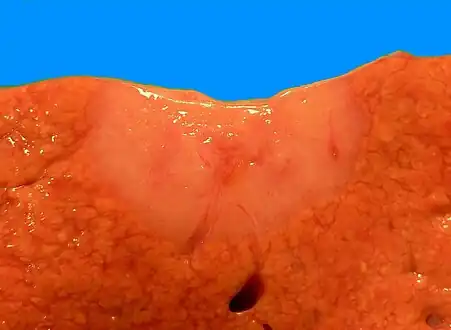

Low magnification micrograph of a bile duct hamartoma. Trichrome stain. Gross pathologic appearance of a large bile duct hamartoma.

Gross pathologic appearance of a large bile duct hamartoma.